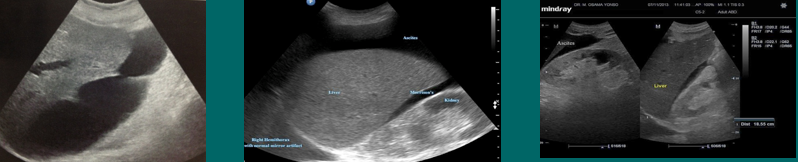

ascites (fluid collection)

pleural effusion (fluid collection)